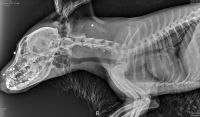

Судя по снимкам, опубликованным в соцсети, на голове щенка видны многочисленные следы от дроби. По словам представителей благотворительной организации, собаке удалось выжить, но ему требуется срочная операция. На приложенных рентген-снимках видно застрявшие в голове металлические шарики. Граждане написали заявление о преступлении.

На снимке видна застрявшая дробь